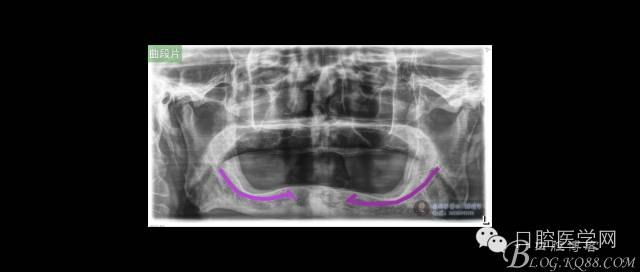

ICX-ON-4即刻負(fù)重